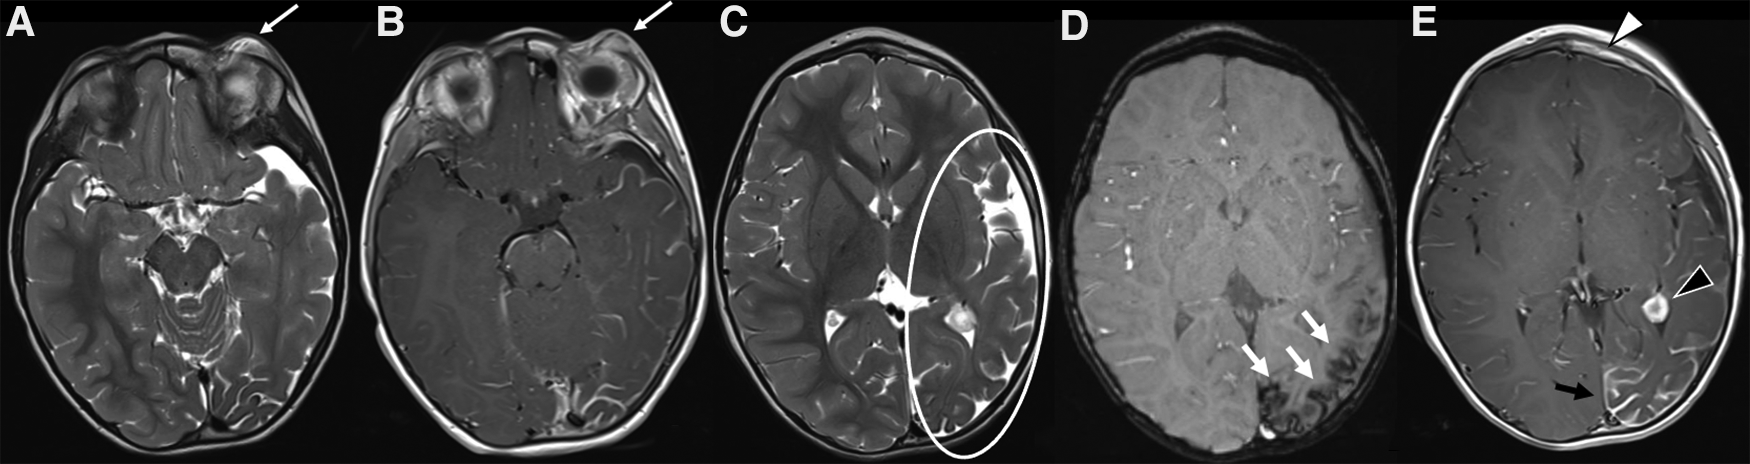

Figure 7. MRI of a 3-year-old child with Sturge-Weber syndrome and a capillary malformation (CM) on the left forehead, upper eyelid and periorbital region (V1 distribution). (A,B) On the left there is an increased thickness of the periorbital soft tissues (particularly of the skin and subcutaneous tissue) corresponding to the clinically visible mark, which shows a subtle hyperintensity on axial T2-weighted sequence and a faint but rather homogeneous enhancement on axial post contrast T1 weighted sequences (white arrows in A and B, respectively). (C–E) Typical associated intracranial features of SWS on the same side (left) of the CM, including atrophy of the cerebral hemisphere with enlargement of subarachnoid spaces (especially in the frontal, insular, parietal and occipital regions, white circle in C), cortical gyral hypointensities due to calcifications on SWI (white arrow in D), contrast enhancement of the leptomeningeal angioma and choroidal plexus hypertrophy on axial post-Gadolinium T1 weighted sequence (black arrow and arrowhead in E, respectively). A subtle enhancement of the left frontal bone is also evident (white arrowhead in E), due to the intra-osseus extension of the overlying CM.